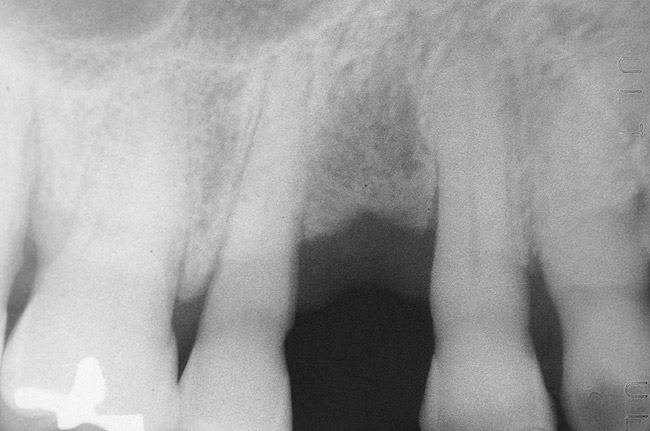

GTR, however, is still a viable option because there is consistency in published data—treating a vertical osseous lesion with this technique results in more clinical attachment gain than just open-flap debridement without performing GTR.46 The success rate in smokers, however, is significantly lower than in nonsmokers.47 Figure 11 and Figure 12] show a case in which tooth No. 22 had a large distal defect. Figure 13 shows the 6-year re-entry photograph, and Figure 14, the 6-year posttreatment radiograph, demonstrating complete clinical fill of the defect. Factors to consider in GTR include defect size (at least 3 mm to 4 mm), number of defect walls (at least two bony walls, but a three-wall defect is the most predictable to treat; Figure 15 shows a one wall defect, which is not graftable), furcation status (furcations are less predictable to obtain increased clinical attachment levels46), and mobility.48 However, patient compliance is critical in regard to both short-term and long-term success rates with GTR.

Figure 11  Very large osseous lesion exposed on tooth No. 22 after scaling and degranulation.

Figure 11

Figure 12  Radiographic view of the case seen in Figure 11.

Figure 12